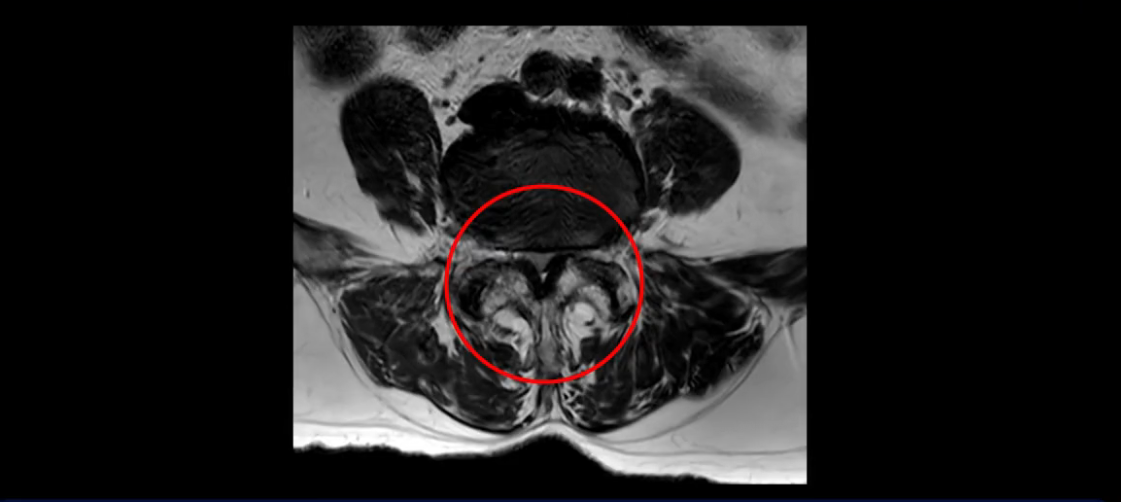

또 척추관협착도 매우 심합니다.

척추관이 심하게 좁아져 있습니다.

이렇게 신경 구멍들이 좁아져 있고 신경이 눌리니까 엉덩이와 다리가 너무 저리고 아파서 아예 일어서질 못하니까 휠체어를 타고 병원에 내원하셨는데요. 그럼 어떻게 이분처럼 신경이 눌려있는 환자분들을 수술 없이 치료해서 잘 걷게 만들고 엉덩이와 다리가 저리고 아픈 증상이 사라지게 할까요? 지금부터 설명해 드립니다.